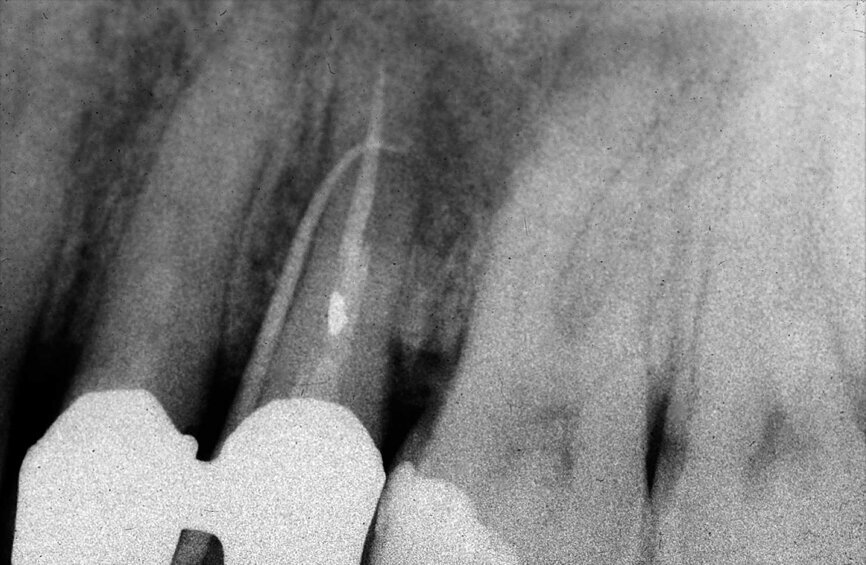

Dans la prémolaire maxillaire présentée dans les figures 5 et 6, le fistulogramme indique la présence d’une lésion apicale, qui s’étend en direction coronaire jusqu’au tiers moyen de la racine. La décision clinique pourrait donc s’orienter vers un retraitement orthograde ; toutefois, le cliché CBCT nous donne une tout autre vision de la situation que celle de la radiographie, dans la mesure où il montre une lésion irréversible de la dent due à un traitement antérieur, et la nécessité de l’extraire.